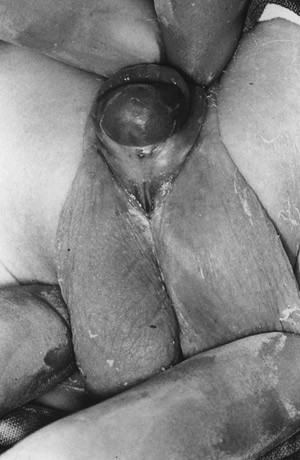

Hypospadias is usually diagnosed during the routine examination after birth (fig 1). While diagnosis is easily established in the presence of an external and visible malformation, less severe disease is sometimes not identified. Depending on the position of the meatus, the condition is classified as glanular/subglanular, penile, penoscrotal or perineal. Most hypospadias are of the distal type; e.g. 69 % of the cases were distal in a Norwegian follow-up study (12) (fig 2). The ventral part of the penis is more or less developed. In addition to a misplaced urethral opening, most affected infants will have a dorsally placed, hood-formed foreskin that does not cover the ventral portion of the glans. In addition, there may be varying degrees of ventral curvature of the penile shaft, and a variably developed corpus spongiosum (fig 3). Some patients have a narrow meatus which requires a meatotomy before final surgical correction. In rare cases, there is also pathological torsion of the penis; there is also an increased occurrence of micro penis. If one or more of these conditions exist despite a normal position of the meatus, the abnormality is usually referred to as «hypospadias». In some cases, parents’ reports of a backward urine flow and/or an increasing downward curvature of the penis when erected can lead to the diagnosis hypospadias. In most cases, careful clinical examination will be sufficient. With proximal types, radiological examination of the urinary tract and hormonal and chromosomal analyses are appropriate. Other urogenital abnormalities may be associated with more pronounced hypospadias with kryptorchism (abdominal retention of the testicles) as one of the most frequent abnormalities.